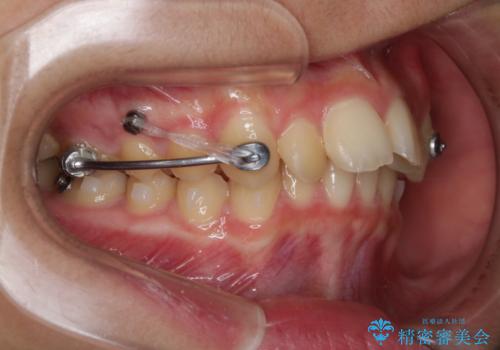

非抜歯で劇的に出っ歯を改善!インビザラインとカリエールの組み合わせ治療

- インビザライン カリエール

- 患者様、出っ歯のお悩みで来院されました。

骨格の分析を行ったところ上顎も出てはいるのですが、下顎が引っ込んでいる状態であるということがわかりました。

よって上顎の歯を抜いて治療をするのではなく、カリエールという器具を使用して下顎を前に引っ張り出しながら上顎を引っ込めるという治療を行うことにしました。